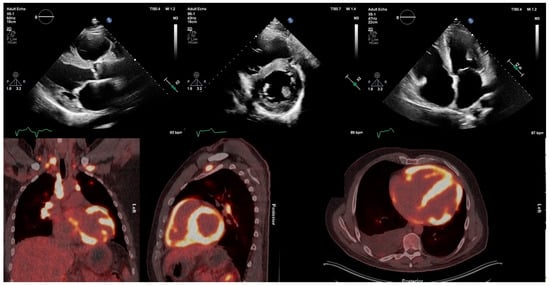

Figure 2.

Transthoracic echocardiogram of patient with active cardiac sarcoidosis demonstrating hypertrophied, echogenic speckled left-ventricular myocardium in regions with high 18F-FDG uptake on PET, particularly the interventricular septum. 18F-FDG = 18F-fluorodeoxyglucose; PET = positron emission tomography.